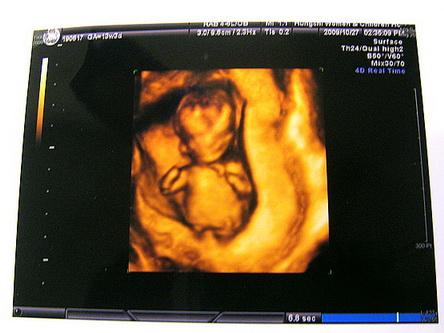

前3個月體虛頭暈嘔吐頻尿習慣了,

後3個月肚腹沈重翻身不易變得理所當然,

肚子挨了一刀,

左右手on上IV回血又脫針腫脹也無所謂,

就懷孕生產這件事來說,

德沃金老頭兒說的體驗利益算是到手,

雖然過程中大多數的情節是摸索和忍耐,

但總是得到可貴而獨一無二的人生經驗。